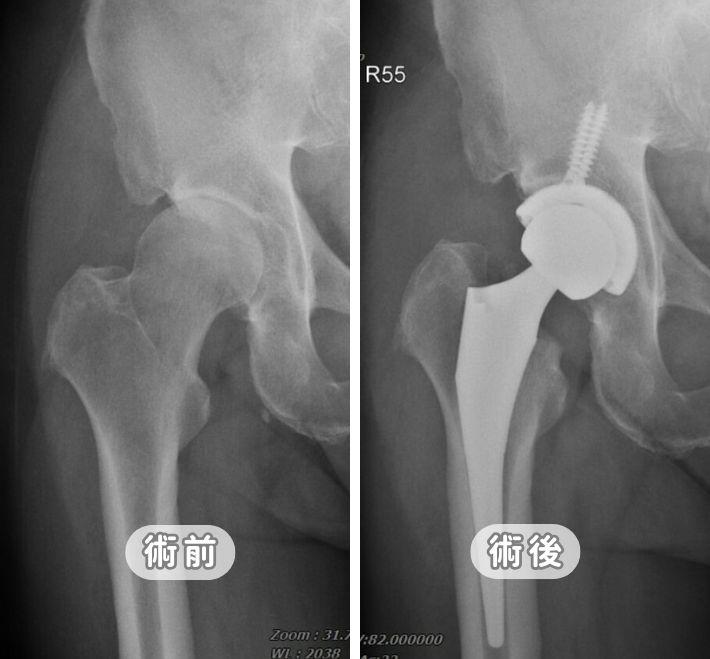

【告別髖關節退化】治療全攻略:新式微創髖關節置換手術以精準醫療解決鼠蹊部痛與長短腳困擾

鼠蹊部疼痛、走路跛行竟是髖關節退化?張建鈞醫師團隊詳解髖關節分級與膝蓋牽涉痛真相。本文解析創新「前外側微創髖關節置換術」,透過 6-8 公分小傷口且完整保留肌肉技術,實現術後 24 小時下床、免復健、低疼痛目標。結合 2025 最新文獻證實,高齡者透過精準醫療也能重獲行走自由。

微創人工髖關節手術全攻略:傷口小、免復健、重新大步走路

髖關節疼痛導致走路吃力、無法蹲下?張建鈞醫師解析「微創人工髖關節置換術」。詳解正位前開與創新前外側技術,如何做到不傷肌肉、術後當天即可下床。內含人工關節材質比較、自費費用建議與術後康復指南,助您精準評估,重拾行動自由。